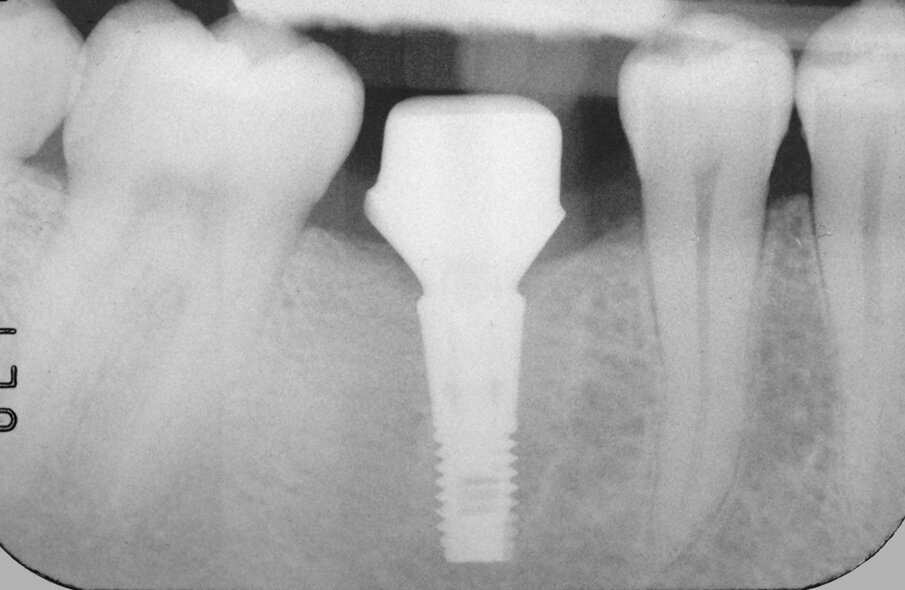

Fig. 15: Verification of correct seating of the abutment using a radiographic image. Note that the transitional portion of the abutment followed the contour of the bone.

Fig. 17: After ten years, the radiograph showed a perfect fit of the restoration, the spaces created for the interproximal papillae and the position of the bone at the level of the implant.